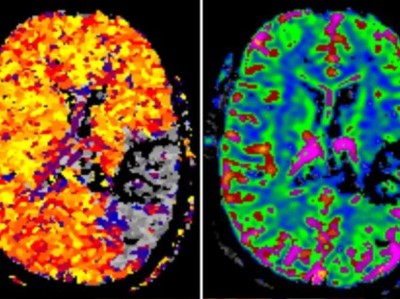

73-Jährige mit Schlaganfall unter DOAK-Therapie – wie würden Sie vorgehen?

Eine 73-jährige Patientin wird aufgrund eines akuten Anfalls mit einer Sprachstörung und einer mäßig ausgeprägten Hemiparese rechts vom Notarzt eingeliefert. Die Patientin war aufgrund eines nicht valvulären permanenten Vorhofflimmerns mit Dabigatran 150 mg BID (2-mal/Tag) antikoaguliert. Wie würden Sie weiter vorgehen?

Akute und chronische intrakranielle Blutungen unter DOAK